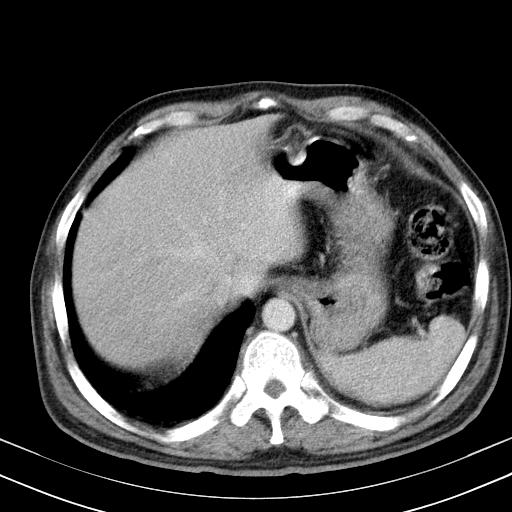

先行ct平扫,纵膈内多发软组织影,ct值约为36hu,以下为增强扫描和腹部平扫。

经典?纵膈多发肿大淋巴结。腹膜后未见异常。

还见胃窦壁增厚!转移亦有可能!

大家看看肝脏右叶片状低密度影是什么改变啊?

淋巴瘤?肝脏请增强后说啊

多发肿大淋巴结影,肝内改变需结合强化观察

多发肿大淋巴结影,肝内改变需结合强化观察。